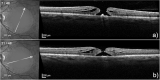

Purpose: The purpose of this study was to develop methods to model the external limiting membrane (ELM) and ellipsoid zone (EZ) within the elevated cuff surrounding a macular hole (MH) to determine if the predicted size of the defect in these layers after virtual flattening was associated with the actual postoperative defect and best-corrected visual acuity (BCVA).

Methods: Patients were included who had undergone successful MH surgery. The defects in the ELM and EZ after virtual flattening were modeled using in-house software. Main outcomes were postoperative defects in ELM and EZ at 2 months and BCVA at 12 months.

Results: Fifty-eight patients were included. BCVA improved from 0.87 (0.31) logMAR pre-operatively to 0.26 (0.21) at 12 months (P < 0.001). For both the ELM and EZ, the predicted virtually flattened pre-operative defects were associated with the actual postoperative defects at 2 months (R2 = 0.33, P < 0.01 and R2 = 0.50, P < 0.01, respectively). There was a significant association of BCVA at 12 months (adjusted R2 = 0.85) with the pre-operative modeled area of the defect in the ELM (P < 0.01) and to a lesser extent with the defect in the EZ (P < 0.01) and base of the MH (P < 0.01).

Conclusions: Virtually flattening of the pre-operative defect in the ELM provides important predictive information of visual acuity. Incorporation of tools into commercially available optical coherence tomography (OCT) devices to facilitate such measurements would provide the clinician with important prognostic information.